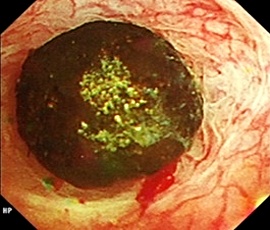

早期大腸がん、腫瘍を切らずに治す低侵襲な内視鏡治療

大腸における早期がんに対する内視鏡治療手技が発達し、根治ができる症例が増加して

おり、従来の治療に代わる新しい治療法として注目されていますが、当院では可能なか

ぎり食道、胃と同様に大腸における早期がんに対しては内視鏡的粘膜下層剥離術

(Endoscopic submucosal dissection、以下ESD)を行っております。

ESD治療の実際

治療手技は内視鏡治療用の電気のメスで直接,病変部を切って剥ぎ取る方法です。高度

な内視鏡治療技術が要求されます。比較的大きな病変も一括切除が可能であるため局所

再発率を下げることや、顕微鏡による正確な病理診断を行い、がんの悪性度を正確に調

べることができることなどのメリットがあります。低侵襲治療と正確な病理診断を兼ね

た非常に優れた内視鏡的治療になりますが、しかし正確な病期診断が不可欠であり、早

期がんに対する各種画像検査を行い治療の適応を決定します。